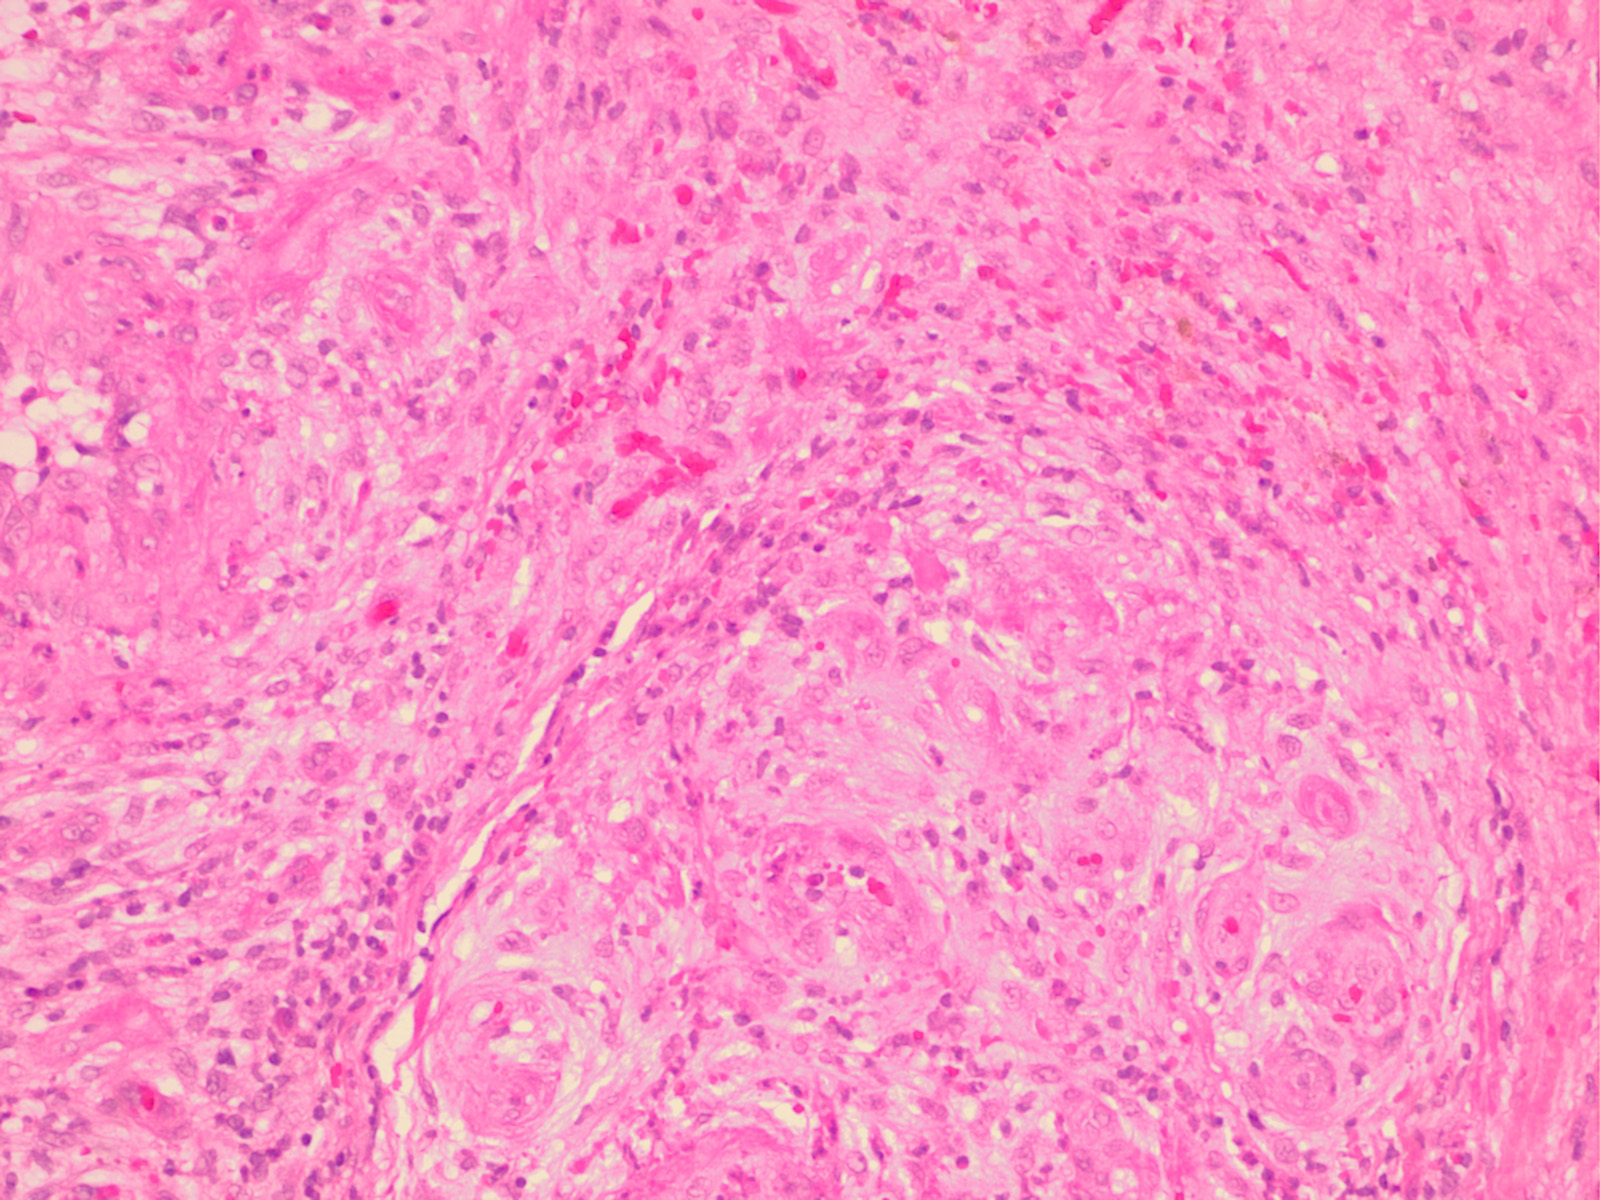

Atrophie blanche =الضمور الابيض